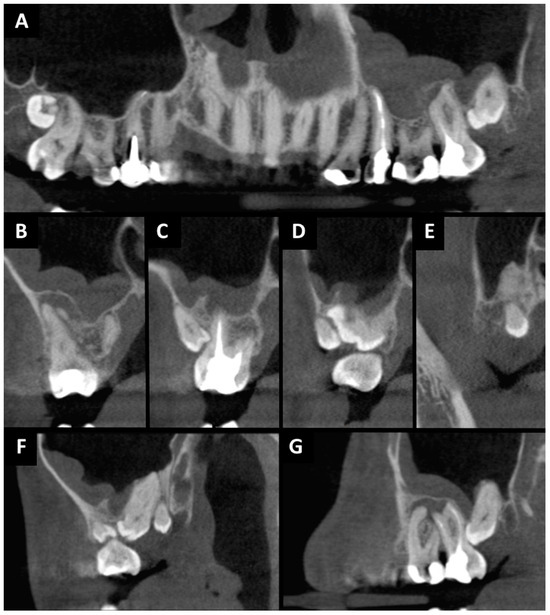

2. Case Presentation